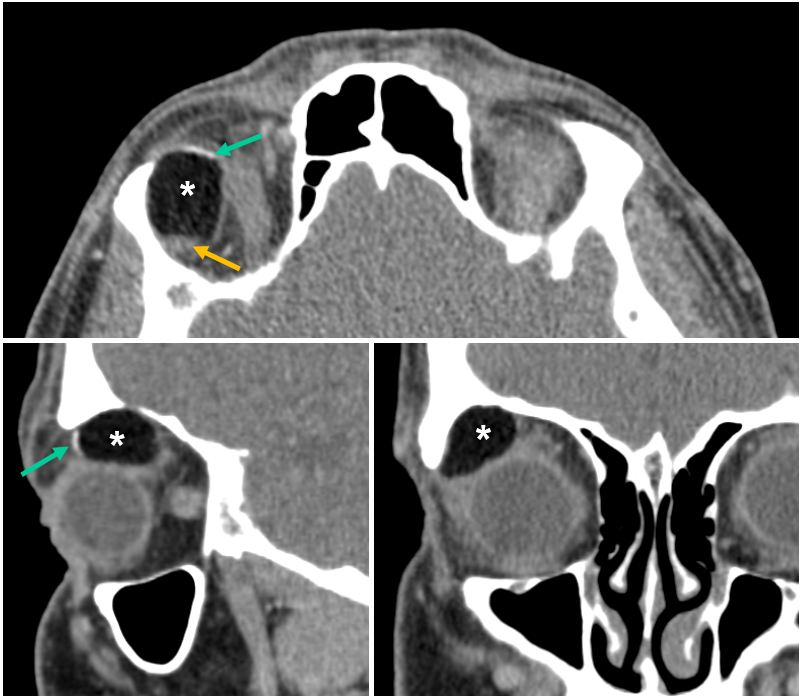

Imagen 1. Imágenes de TC orbitario tras la administración de CIV. Se evidencia masa en cuadrante superior externo de la órbita derecha, en topografía de glándula lacrimal. Presenta morfología ovalada y márgenes lisos, con valores de atenuación grasa (*) y componente lineal de densidad calcio (flecha verde) en polo anterior y de partes blandas en polo posterior (flecha amarilla).

No se observan signos inflamatorios ni repercusión del plano óseo subyacente.

Quiste orbitario del desarrollo (dermoides, epidermoides y teratoma).

Los quistes orbitarios surgen de la inclusión de un elemento ectodérmico durante el cierre del tubo neural, donde los elementos dérmicos quedan atrapados en la línea de sutura, diploe, meninges o cuero cabelludo. Los quistes dermoides y epidermoides se encuentran con mayor frecuencia en el cuadrante temporal superior de la órbita, adyacente a la línea de sutura cigomático-frontal.

La mayoría de estas lesiones son de crecimiento lento, aunque algunas pueden crecer rápidamente en adultos. Se observan como masas de densidad grasa que no realzan tras la administración de contraste intravenoso.

Los quistes dermoides presentan densidades de grasa y calcio.

Los quistes epidermoides pueden exhibir características de imagen similares, pero la calcificación no es una característica habitual.